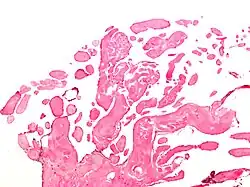

Micrograph of a papillary fibroelastoma, a benign tumor of heart valves. H&E stain. | |

- Papillary fibroelastoma

A subset of the primary tumors of the heart are tumors that are found on the valves of the heart. Tumors that affect the valves of the heart are found in an equal distribution among the four heart valves.[2] The vast majority of these are papillary fibroelastomas. Primary tumors of the valves of the heart are more likely to occur in males. While most primary tumors of the valves of the heart are not malignant, they are more likely to have symptoms related to the valve, including neurologic symptoms and (in a few cases) sudden cardiac death.